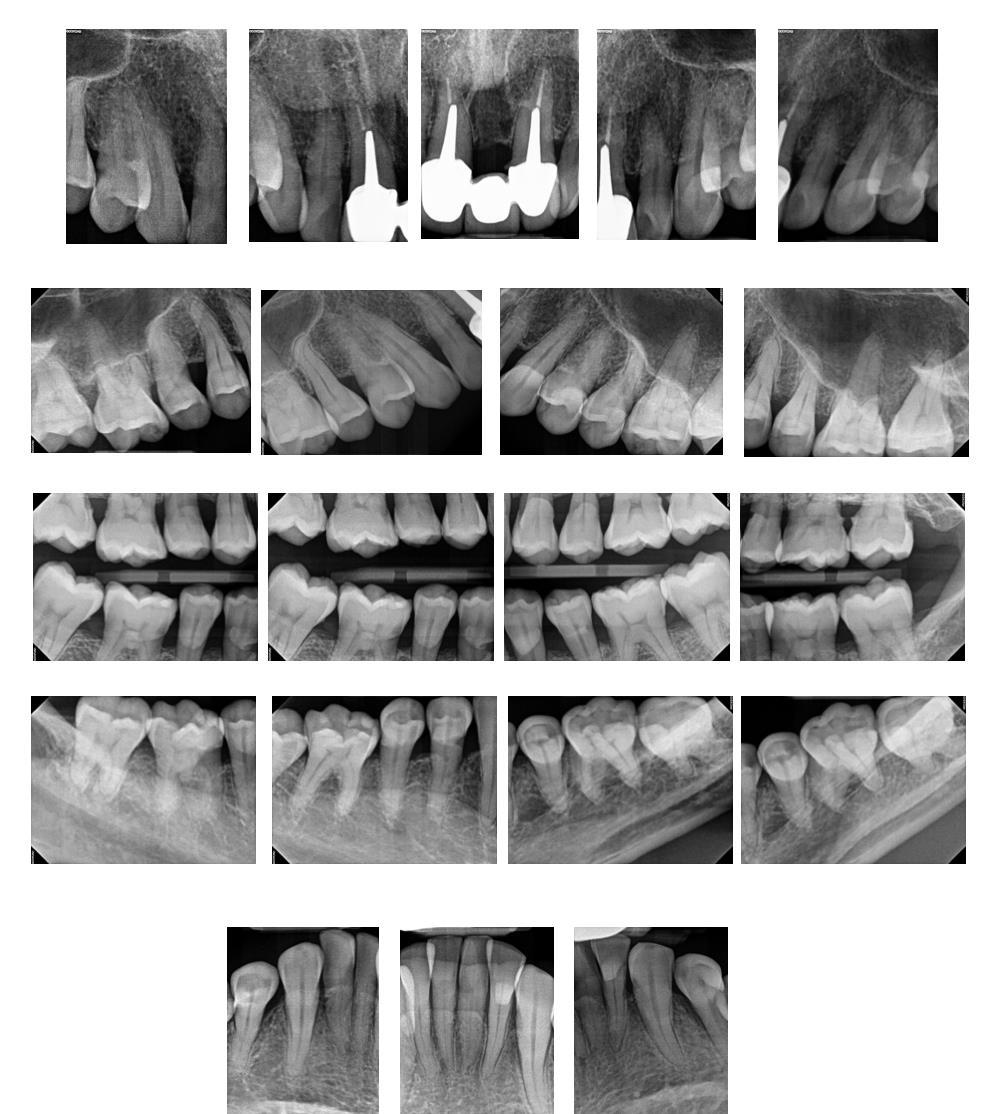

Radiographic findings

• No suspicious areas

• Calculus

• Generalized 15-30% boneloss

• Localized vertical boneloss

• Thinning ofthe lamina dura